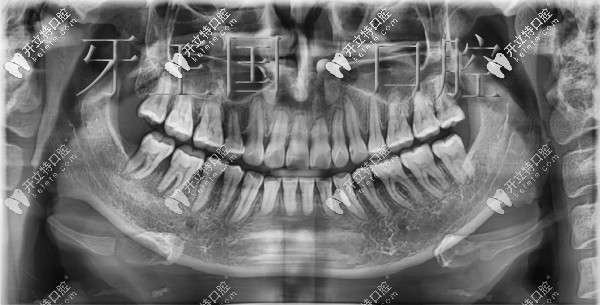

在西固區(qū)牙王國口腔做舌側(cè)矯正前后對比圖:

矯正前▼